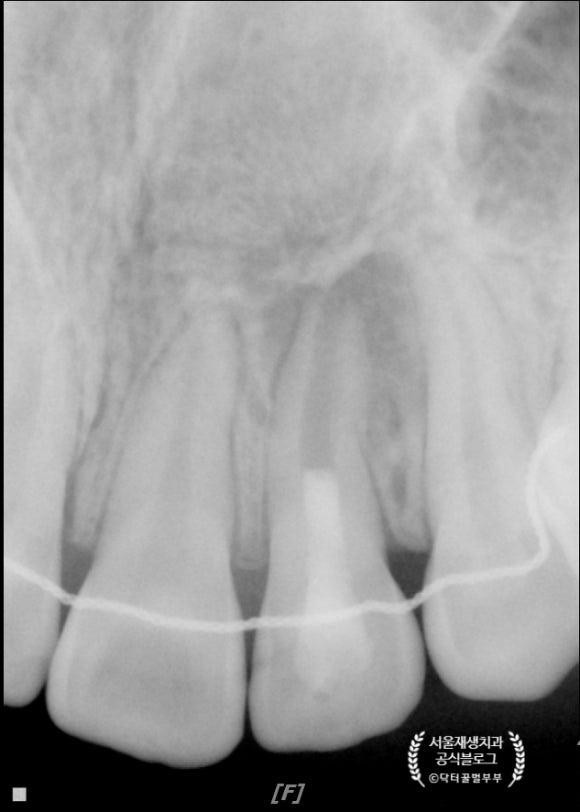

4개월 후에 왔습니다.

햇살 무늬처럼 가장자리에서부터 뼈가 재생되는 것, 이제는 보이시지요?^^